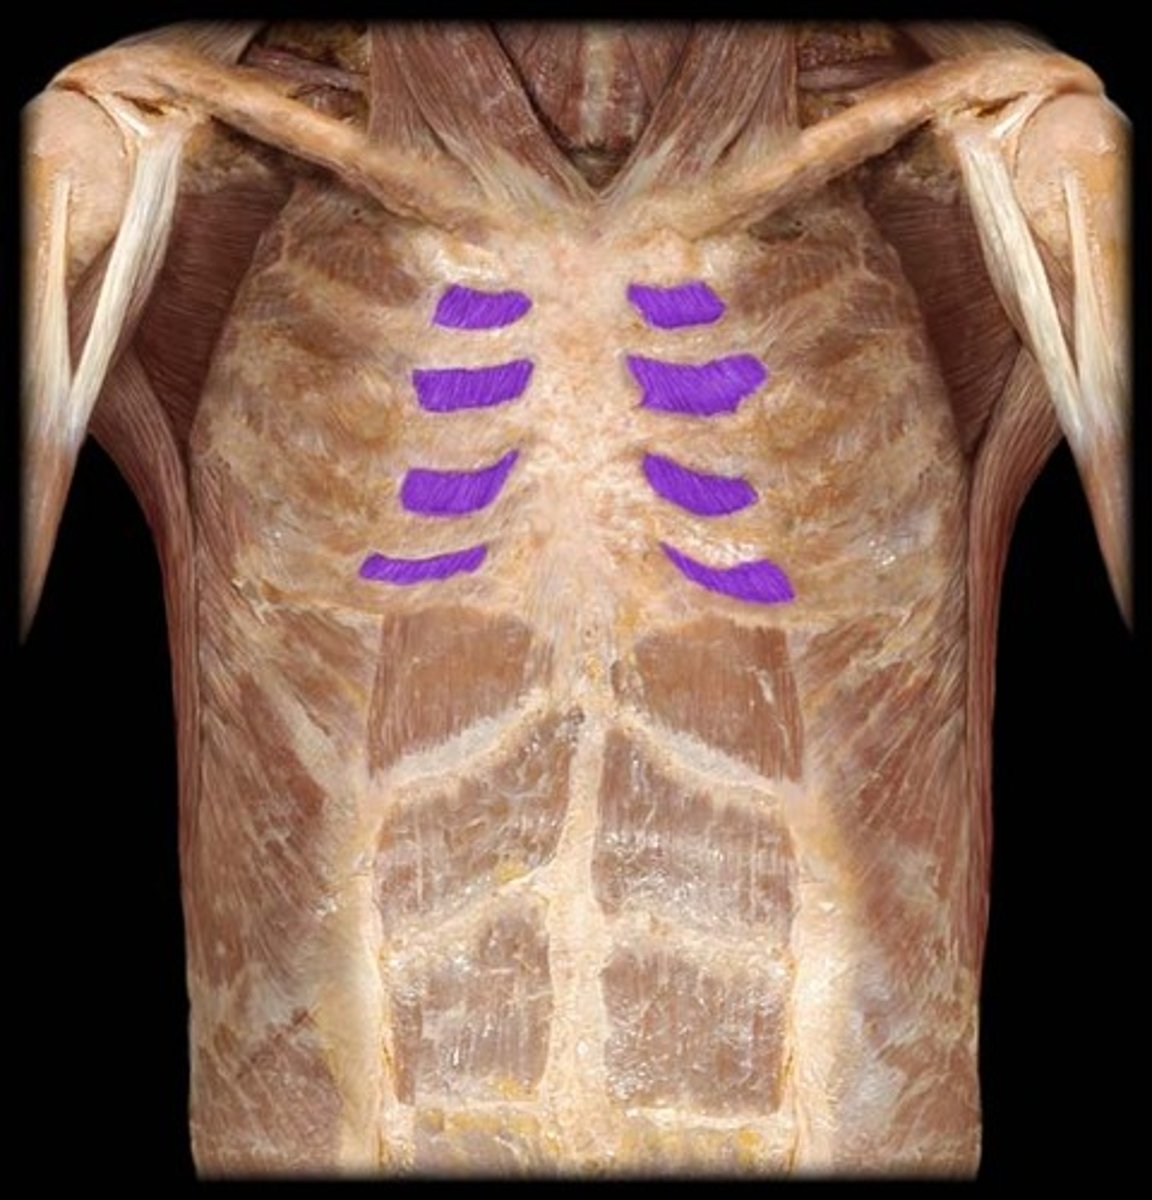

External intercostals

Origin: Inferior margins of ribs 1-11

Insertion: Superior margin of next lower rib

Action: when scalenes fix rib 1, external intercostals elevate and protract ribs 2-12, expanding the thoracic cavity and creating a partial vacuum causing inflow of air

Internal intercostals

Origin: Superior margins and costal cartilages of ribs 2-12; margin of sternum

Insertion: Inferior margin of next higher rib

Action: During inspiration, the intercartilaginous part aids in elevating the ribs and expanding the thoracic cavity. Expiration, incartilaginous part depresses and retracts the ribs and compresses the thoracic cavity expelling air

Pectoralis minor

Origin: Ribs 3-5 and overlying fascia

Insertion: Coracoid process of scapula

Action: With serratus anterior, draws scapula laterally and forward around chest wall; with other muscles, rotates scapula and depresses apex of shoulder

Serratus anterior

Origin: All or nearby all ribs

Insertion: Medial border of scapula

Action: With pectoralis minor, draws scapula laterally and forward around chest wall; protracts scapula, and is the prime mover in all forward-reaching and pushing actions; fixes scapula during abduction of arm